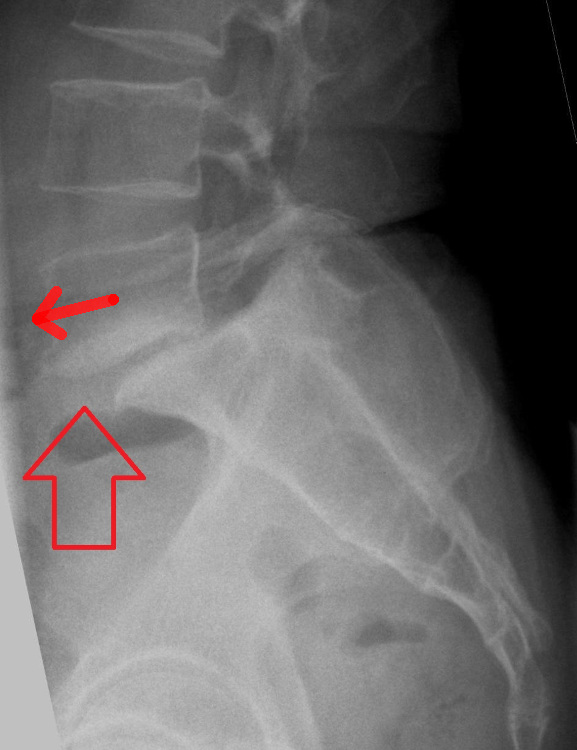

Spondilolistesi

- Descrizione: Spostamento in avanti di una vertebra rispetto alla vertebra sottostante. Ne sono descritte cinque tipologie:

I sintomi sono: Dolore in zona lombosacrale e Sciatica da Radicolopatia, sintomi della Stenosi vertebrale.